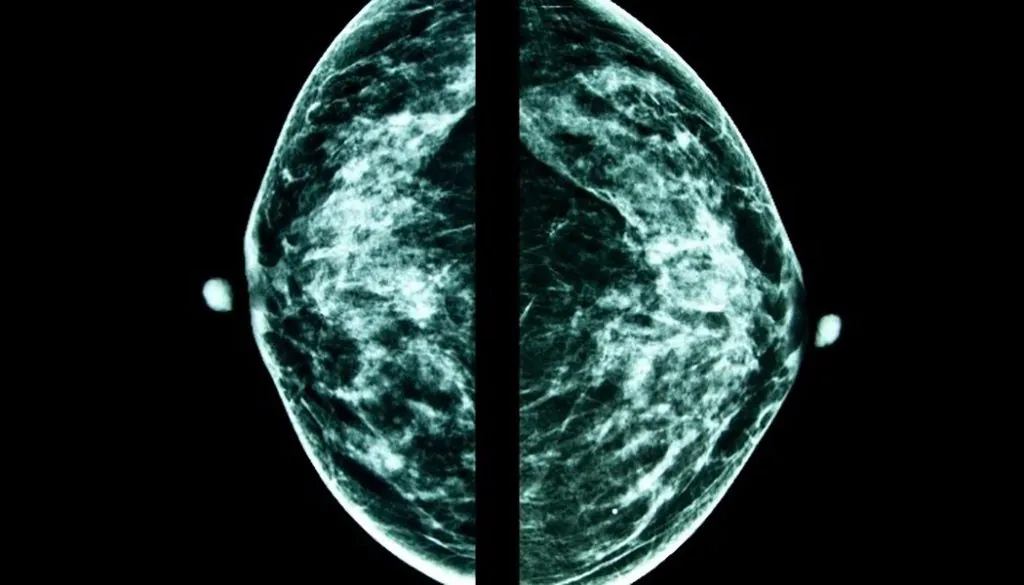

Having a mammogram allows medical professionals to examine an x-ray of the breast tissue and look for any abnormalities or hints of cancer that other methods may not be able to detect. Having regularly scheduled mammograms presents an opportunity for early diagnosis, which significantly increases the chance for successful treatment. As signs and symptoms are often difficult to observe at early stages, mammograms have been the gold standard used for cancer detection and may reduce mortality by up to 40%. Because of this, the United States Preventative Services Task Force recommends that women aged 50-74 undergo a mammography every two years.

Mammograms have greatly improved the likelihood of beating breast cancer. In fact, over 3.1 million survivors live in the United States. As with all technologies, mammograms are constantly evolving to provide the highest quality of care for patients. The mammograms used today emit limited amounts of radiation, causing minimal harm to women receiving screenings. In fact, the amount of radiation received from a mammogram is equal to that obtained from the natural environment in less than two months. The benefits of early detection greatly outweigh any potential risk of radiation exposure.